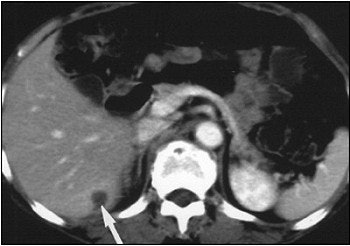

A 62-year-old woman with heterogeneous cyst of the liver. Abdominal CT scan (above) shows heterogeneous cystic lesion with suspected parenchymal liver metastasis (arrow), but not peritoneal implants on liver surface. Whole-body FDG-PET (below) scan in maximum intensity projection does not indicate significant FDG uptake in liver parenchyma (thin arrows) beside hot spot at liver surface (thick arrow). Yoshida Y, Kurokawa T, Kawahara K, Tsuchida T, Okazawa H, Fujibasyashi Y, Yonekura Y, Kotsuji F, "Incremental Benefits of FDG Positron Emission Tomography over CT Alone for the Preoperative Staging of Ovarian Cancer," (AJR, January 2004, Vol.182, pp. 227-233).